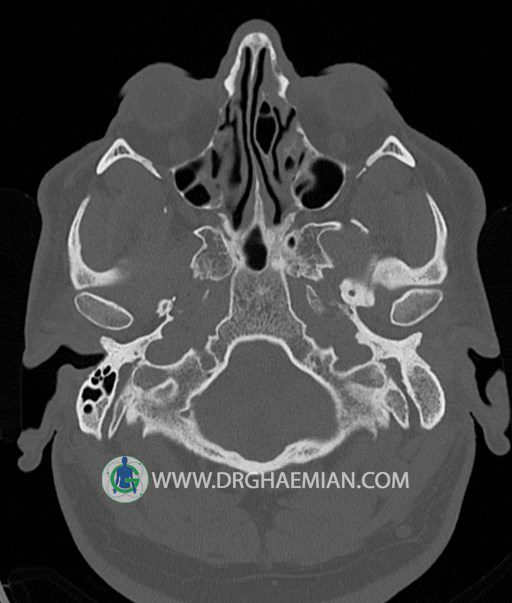

سی تی اسکن گوش داخلی به رادیولوژیست اجازه می دهد تا سطوح مختلف، یا اسلایس هایی از استخوان های که از جمجه به گوش می روند را از طریق امواج ایکس چرخشی مشاهده کند. در این کیس اودیت مدیا، ماستوئیدیت مزمن، اوتیت خارجی، انحراف سپتوم بینی، کونکا بولوزا و افزایش ضخامت سینوس ها مشاهده می شود.

گزارش پزشک :

در HRCT از استخوان تمپورال با مقاطع آگزيال ، ساژيتال و کرونال ظريف ( 0.6 mm ) :

– نماي کوکلهآي دو طرف با 2.5 دور گردش مجرا

– نماي cochlear aqueduct

– نماي semicircular canal خلفي ، لترال ، فوقاني و وستيبول

– استخوانچه هاي گوش داخلي شامل malleus ، incus و stapes (دنسيتي و رديف استخوانچه ها )

– نماي oval window و round window ، tympanic cavity ، attic و کانال گوش داخلي

– کانال عصب فاشيال و مسير ان از ناحيه کانال گوش داخلي ، geniculate ganglion تا محل خروج ان از stylomastoid foramen

– نماي tympanic membrane ، کانال ICA ، بولب جوگولار دو طرف

در حد طبيعي است .

– اپاسيتي گوش مياني چپ ناشي از وجود دانسيته نسج نرمي دراطراف استخوانچه ها همراه با اروژن اسکوتوم و

استخوانچه ها بدون جابجايي در رديف استخوانچه ها مشهود است که مطرح کننده اوتيت مديا همراه با نشانه

هاي مشکوک به کولستئاتوم مي باشد .

– اپاسيتي و اسکلروزيس ماستوئيد چپ نشانه ماستوئيديت مزمن

– اپاسيتي کانال گوش خارجي ناشي از دانسيتي نسج نرمي مطرح کننده external otitis

– انحراف سپتوم مياني بيني به راست

– کونکا بولوزا در کونکاي مياني چپ و

– افزايش ضخامت مخاطي در سينوس هاي اتموئيد و ماگزيلاري

اپاسيته